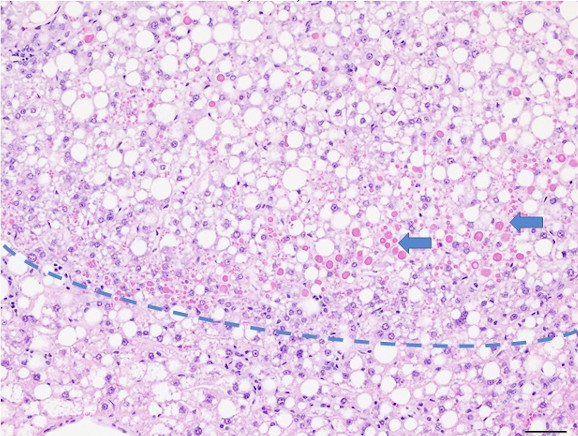

Figure 5: MASH B6 have hepatic crown-like structures (hCLS), a unique histological finding from MASH patients. Hepatic crown-like structures (blue arrowheads) are macrophages surrounding hepatocytes with large lipid vacuoles. Macrophages also form solid inflammatory cell aggregates with other leukocytes (red arrowheads).

Figure 6: Histopathology for C57BL/6NTac mice placed on D09100310 diet (MASH B6NTac) or kept on chow diet (Control B6NTac) from 6 weeks of age. Animals were on diet for 27, 35 or 53 weeks. Hematoxylin and eosin (H&E) staining illustrates morphological changes including steatosis and infiltration of immune cells. Activated HSCs were identified in liver sections by using a rabbit polyclonal antibody to alpha-smooth muscle actin (a-SMA) (1:500 dilution; ab5694; Abcam, Cambridge, MA) which was detected by an anti-rabbit IgG embedded polymer with embedded horseradish peroxidase and visualized with 3,3′-diaminobenzidine (DAB) chromogen (Agilent, Carpentaria, CA). Hepatocellular lipid droplets were identified by visualization of the lipid-binding protein adipophilin known to be expressed in steatotic livers. Sections of livers were probed using a rabbit polyclonal anti-adipophilin antibody (1:200 dilution; NB110-40877, Novus Biologics, Littleton, CO) which was detected by an anti-rabbit IgG embedded polymer with embedded horseradish peroxidase and visualized with 3,3′-diaminobenzidine (DAB) chromogen (Aligent, Carpentaria, CA). Picrosirius red (PSR) staining illustrates collagen I and III fibers and is used to measure fibrosis. The same individual MASH or control animal is shown for all four stains in a particular time point. Different individual animals were used for each time point (i.e. data is not longitudinal by animal). Histopathology services provided by IDEXX BioAnalytics.